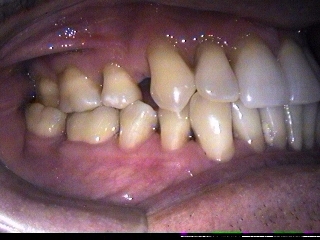

Restaurações de abrasões de tecido

dentário ao nível do colo dental, com resina composta.

ANTES